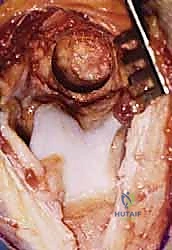

سُميت هذه العملية تيمناً بالجراحين اللذين قاما بتطويرها. تعتمد الفكرة الأساسية لهذه الجراحة العبقرية على مبدأ ميكانيكي بسيط ولكنه فعال للغاية. في الكوع المتيبس بسبب الخشونة، تتكون نتوءات عظمية في الجزء الأمامي (الناتئ الإكليلي والحفرة الإكليلية) والجزء الخلفي (الناتئ الزجي والحفرة الزجية).

بدلاً من إجراء شق جراحي أمامي وشق جراحي خلفي كبيرين للوصول إلى هذه النتوءات، يتم الوصول إلى المفصل من الخلف فقط. يقوم الدكتور هطيف بإزالة النتوءات العظمية الخلفية، ثم يقوم بـ إحداث ثقب (Fenestration) أو نافذة دقيقة في العظم الرقيق الفاصل بين الحفرة الزجية (الخلفية) والحفرة الإكليلية (الأمامية) لعظمة العضد.

هذا الثقب يحقق فوائد مذهلة:

1. يسمح للجراح بالرؤية والوصول إلى النتوءات العظمية الأمامية والأجسام الحرة وإزالتها من خلال هذا الثقب دون الحاجة لفتح الكوع من الأمام.

2. يخلق مساحة إضافية (فراغ) يسمح لطرف عظمة الزند بالدخول فيه أثناء فرد الكوع بالكامل، مما يزيل الاحتكاك ويزيد من نطاق الحركة فوراً.

3. يقلل الضغط داخل المفصل، مما يخفف الألم بشكل ملحوظ.